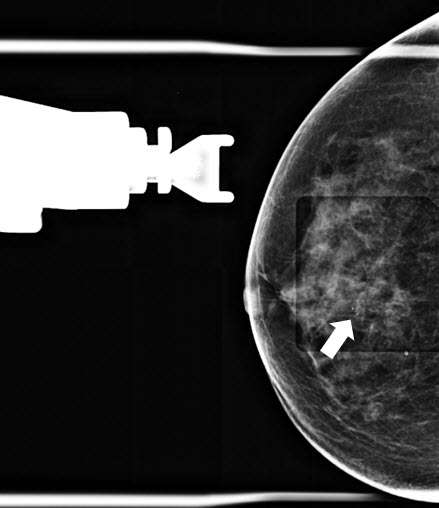

• Technologist takes a stereotactic pair of images (+/- 15 degrees) and radiologist confirms accurate trajectory (Figure 3).

Figure 3. Prefire stereotactic pair of CC images taken +/- 15 degrees.

• Technologist repeats stereotactic pair (+/- 15 degrees) and radiologist confirms accurate trajectory on the postfire images (Figure 4).

Figure 4. Postfire stereotactic pair of CC images taken +/- 15 degrees oblique.